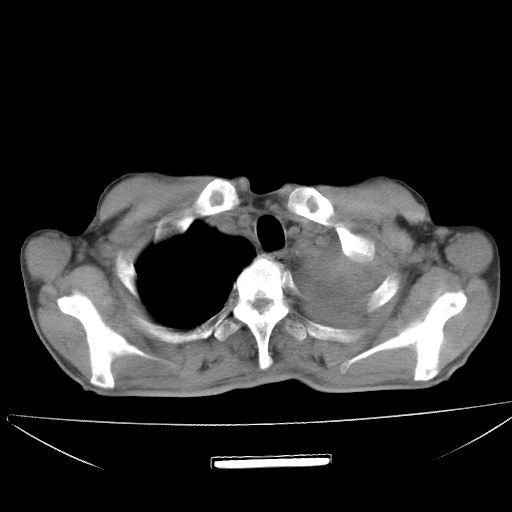

以下是引用杀毒软件在2009-4-28 17:58:00的发言:[br]考虑----左肺慢性肺脓肿形成继发上叶含气不良---抗炎后复查---待排肿瘤所致[br][br][本贴已被 杀毒软件 于 2009-4-28 18:01:26 修改过]